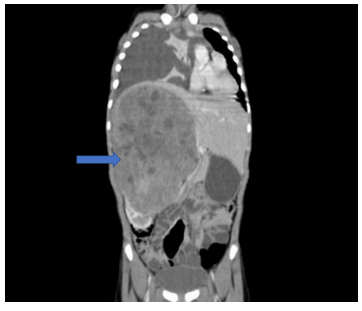

Contrast Enhanced Computed Tomography (CECT) of abdomen showed a large, heterogeneously enhancing mass (22x16x14cm) with multiple necrotic areas arising from the mid and upper pole of the right kidney (Fig 2).

Figure 2: CECT abdomen showing a large heterogeneously enhancing mass with necrotic areas in the right retroperitoneum having “claw sign” arising from the right kidney and extending across the midline to the left side with a normal left kidney. Right sided massive pleural effusion with adjacent passive atelectasis.